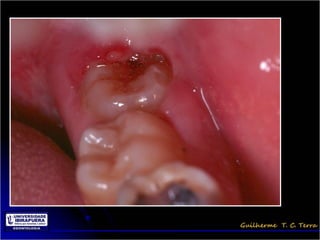

Pericoronarite

• Infecção dos tecidos moles (Opérculo)

que recobrem a coroa de um dente

incluso

• A dificuldade de higienização sob o

opérculo